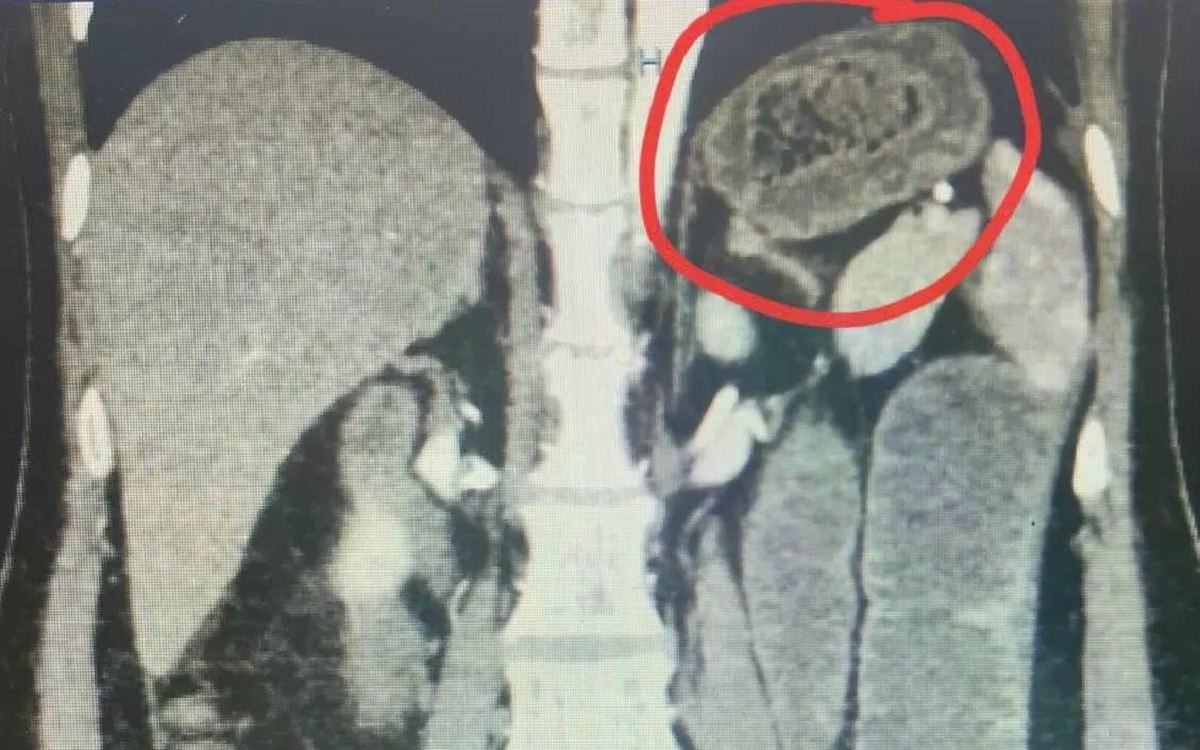

Sau khi thăm khám, kết quả hình ảnh trên phim chụp CT cho thấy hình ảnh một dị vật nằm trong lòng quai ruột non vùng rốn gây thủng ruột.

Dị vật được xác định là một chiếc xương cá sắc nhọn, kích thước lên tới 30,3 mm. Đây là một kích thước rất lớn đối với dị vật đường tiêu hóa. Nguy hiểm hơn, chiếc xương này đã di chuyển qua dạ dày và mắc kẹt tại ruột non, đâm thủng thành ruột.